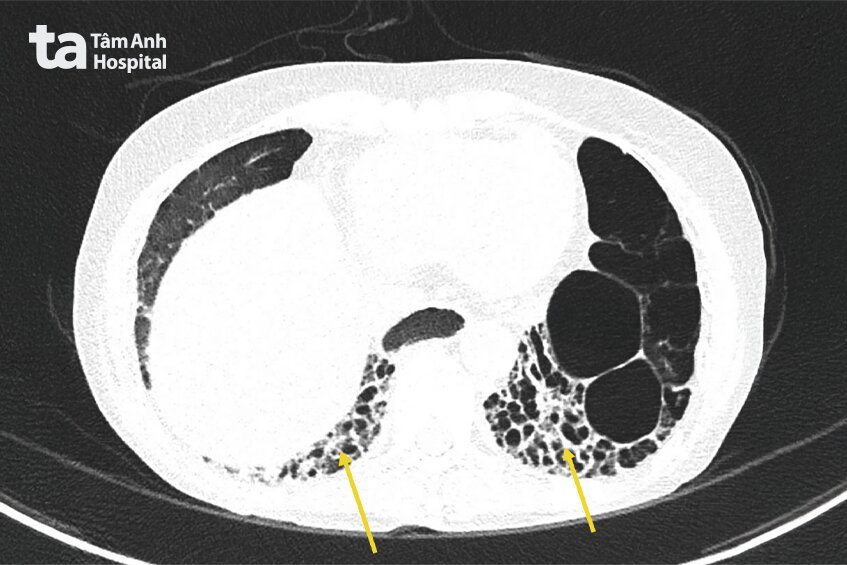

Kết quả cho thấy bệnh xơ cứng bì đã âm thầm phá hoại nhiều cơ quan, trong đó nghiêm trọng nhất là tăng áp động mạch phổi nặng với mức PAPs:78mmHg, cao gần gấp 3 lần so với mức bình thường và tổn thương phổi kẽ khiến giảm trao đổi oxy máu, gây khó thở dai dẳng. Người bệnh cũng có co thắt mạch máu ngoại biên (Raynaud) mức độ nặng, nguyên nhân trực tiếp gây hoại tử đầu ngón tay do máu không thể nuôi dưỡng các đầu chi. Đặc biệt, thăm khám phát hiện thực quản giãn đoạn ngực và giảm nhu động – biến chứng điển hình của xơ cứng bì theo hướng dẫn EULAR/ACR (Liên đoàn Chống Thấp khớp châu Âu/Hội Thấp khớp Hoa Kỳ), khiến thức ăn khó di chuyển xuống dạ dày, gây triệu chứng nghẹn, ứ đọng và trào ngược axit mạn tính, là lý do bà Mỹ sụt cân và suy kiệt kéo dài.

“Nếu không được theo dõi và điều trị đúng phác đồ, xơ cứng bì có thể tiến triển tới giảm chức năng phổi nghiêm trọng do tổn thương phổi kẽ và suy tim phải thứ phát do tăng áp động mạch phổi”, bác sĩ Tân nói.